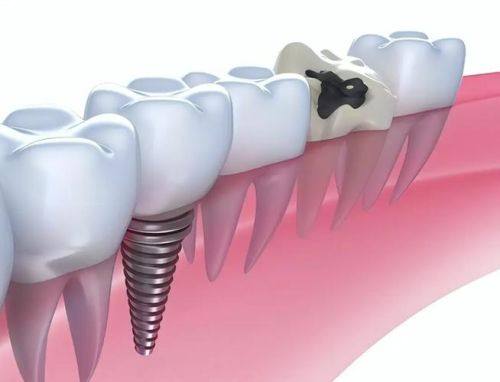

3. 即刻负重种植:即刻负重种植是在种植体植入后,立即安装临时牙冠,让患者在种植手术后就能修复一定的咀嚼功能。高医生在即刻负重种植方面有着不错的技术。他会根据患者的口腔情况和种植体的稳定性,选择合适的负重方案。在手术过程中,他会确保种植体的初期稳定性,为患者提供良好的治疗成效。